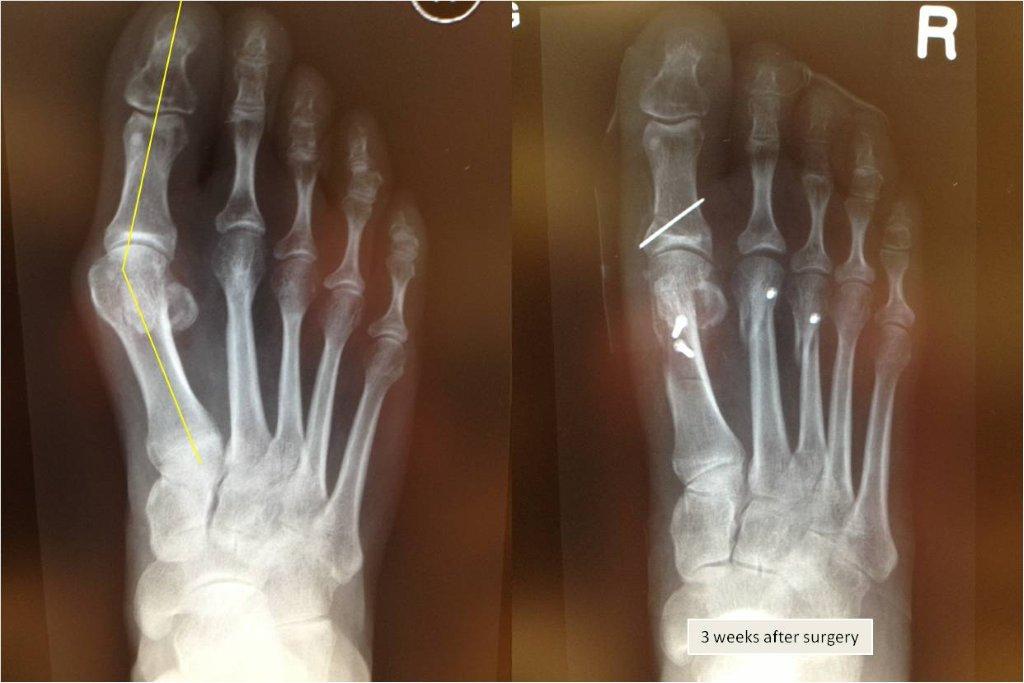

Minimally Invasive Bunion Surgery What You Need to Know The Frankel What Age Can You Get Bunion Surgery most people who have bunion surgery can resume their usual activities in six to 12 weeks. your surgeon will take factors like your age, activity level, overall health, and the severity of the bunion into account when deciding on which. when is surgery needed for bunions? For optimum results, bunion surgery should be done between the ages. What Age Can You Get Bunion Surgery.

Minimally Invasive Bunion Surgery What Age Can You Get Bunion Surgery For optimum results, bunion surgery should be done between the ages of 18 and 60. when is surgery needed for bunions? most people who have bunion surgery can resume their usual activities in six to 12 weeks. An orthopaedic surgeon shares what to do before considering surgery. bunion surgery (bunionectomy) is surgery to remove a bunion from. What Age Can You Get Bunion Surgery.